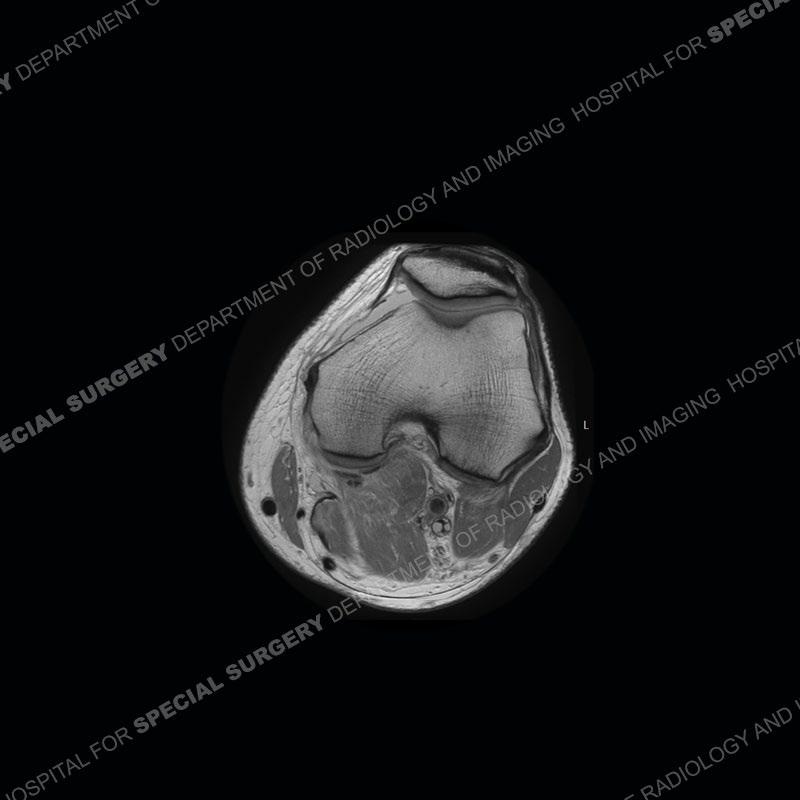

Findings

The radiographs show degenerative change of the medial compartment and a varus knee, but they are not germane to this case. No acute bony injury is present. The MRI shows edema of the posterior medial knee/soft tissue and a focal area of a partially disrupted low signal structure. The details are kept at a minimum in the findings of this case on purpose.

Diagnosis: Partial Disruption Medial Head Gastrocnemius (MHG)

The findings were kept purposefully vague as identifying the structures early on takes away a lot of the diagnosis. An uncommon entity and one of which we do not see a lot. Enthesopathic changes and tendinosis are seen as are distal MHG injuries, but proximal tears are rarely present. This case highlights a number of points. One, it almost always comes down to anatomy. Perhaps not a structure we normally spend too much time on, except save for diagnosing a Baker’s cyst, but knowing where this structure and all structures exist in all three planes is imperative. Second, when you think you are making a “call” or finding that you have never made before, step back and think is this just the abnormal presentation of a common pathology. That situation arises much more frequently. Third, if you look at it once, twice, and probably a third time and are confident in your odd or very rare diagnosis, stick to your guns. Especially, when it comes down to anatomic structures, the proof will be in the images.

Fourth, use all imaging planes and different pulse sequences to make your diagnosis. The edema highlighted in this case can be seen as the obscuration of fat on the PD images but is much easier to perceive as the high signal on the IR pulse sequences. The actual disruption of the MHG myotendinous junction is only able to be seen on the axial images. On the sagittal and coronal images, we get a sense something is wrong but hard to be exact. Lastly, when you look at a study and something just seems off (as I would say the sagittal and coronal images do with that dark band of tissue posteriorly), listen to yourself and go through the study slowly and meticulously. Most of the time you will find you were right, and something indeed is present.